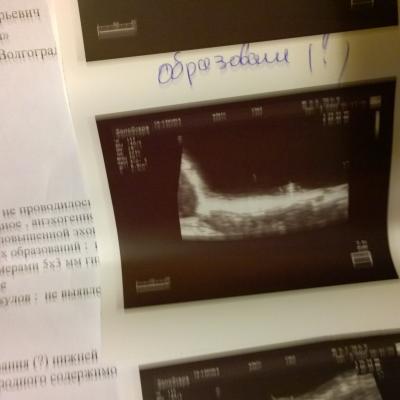

Образование в мочевом пузыре

Здравствуйте. При узи МП нашли образование на нижней стенке, фото прилагаю.

Насколько вероятно, что это доброкачественное? Анализ крови-повышен гемоглобин 161, моноциты 12%. в Моче эритроциты 9-10 в п\з, лейкоциты 2-3 в п\з